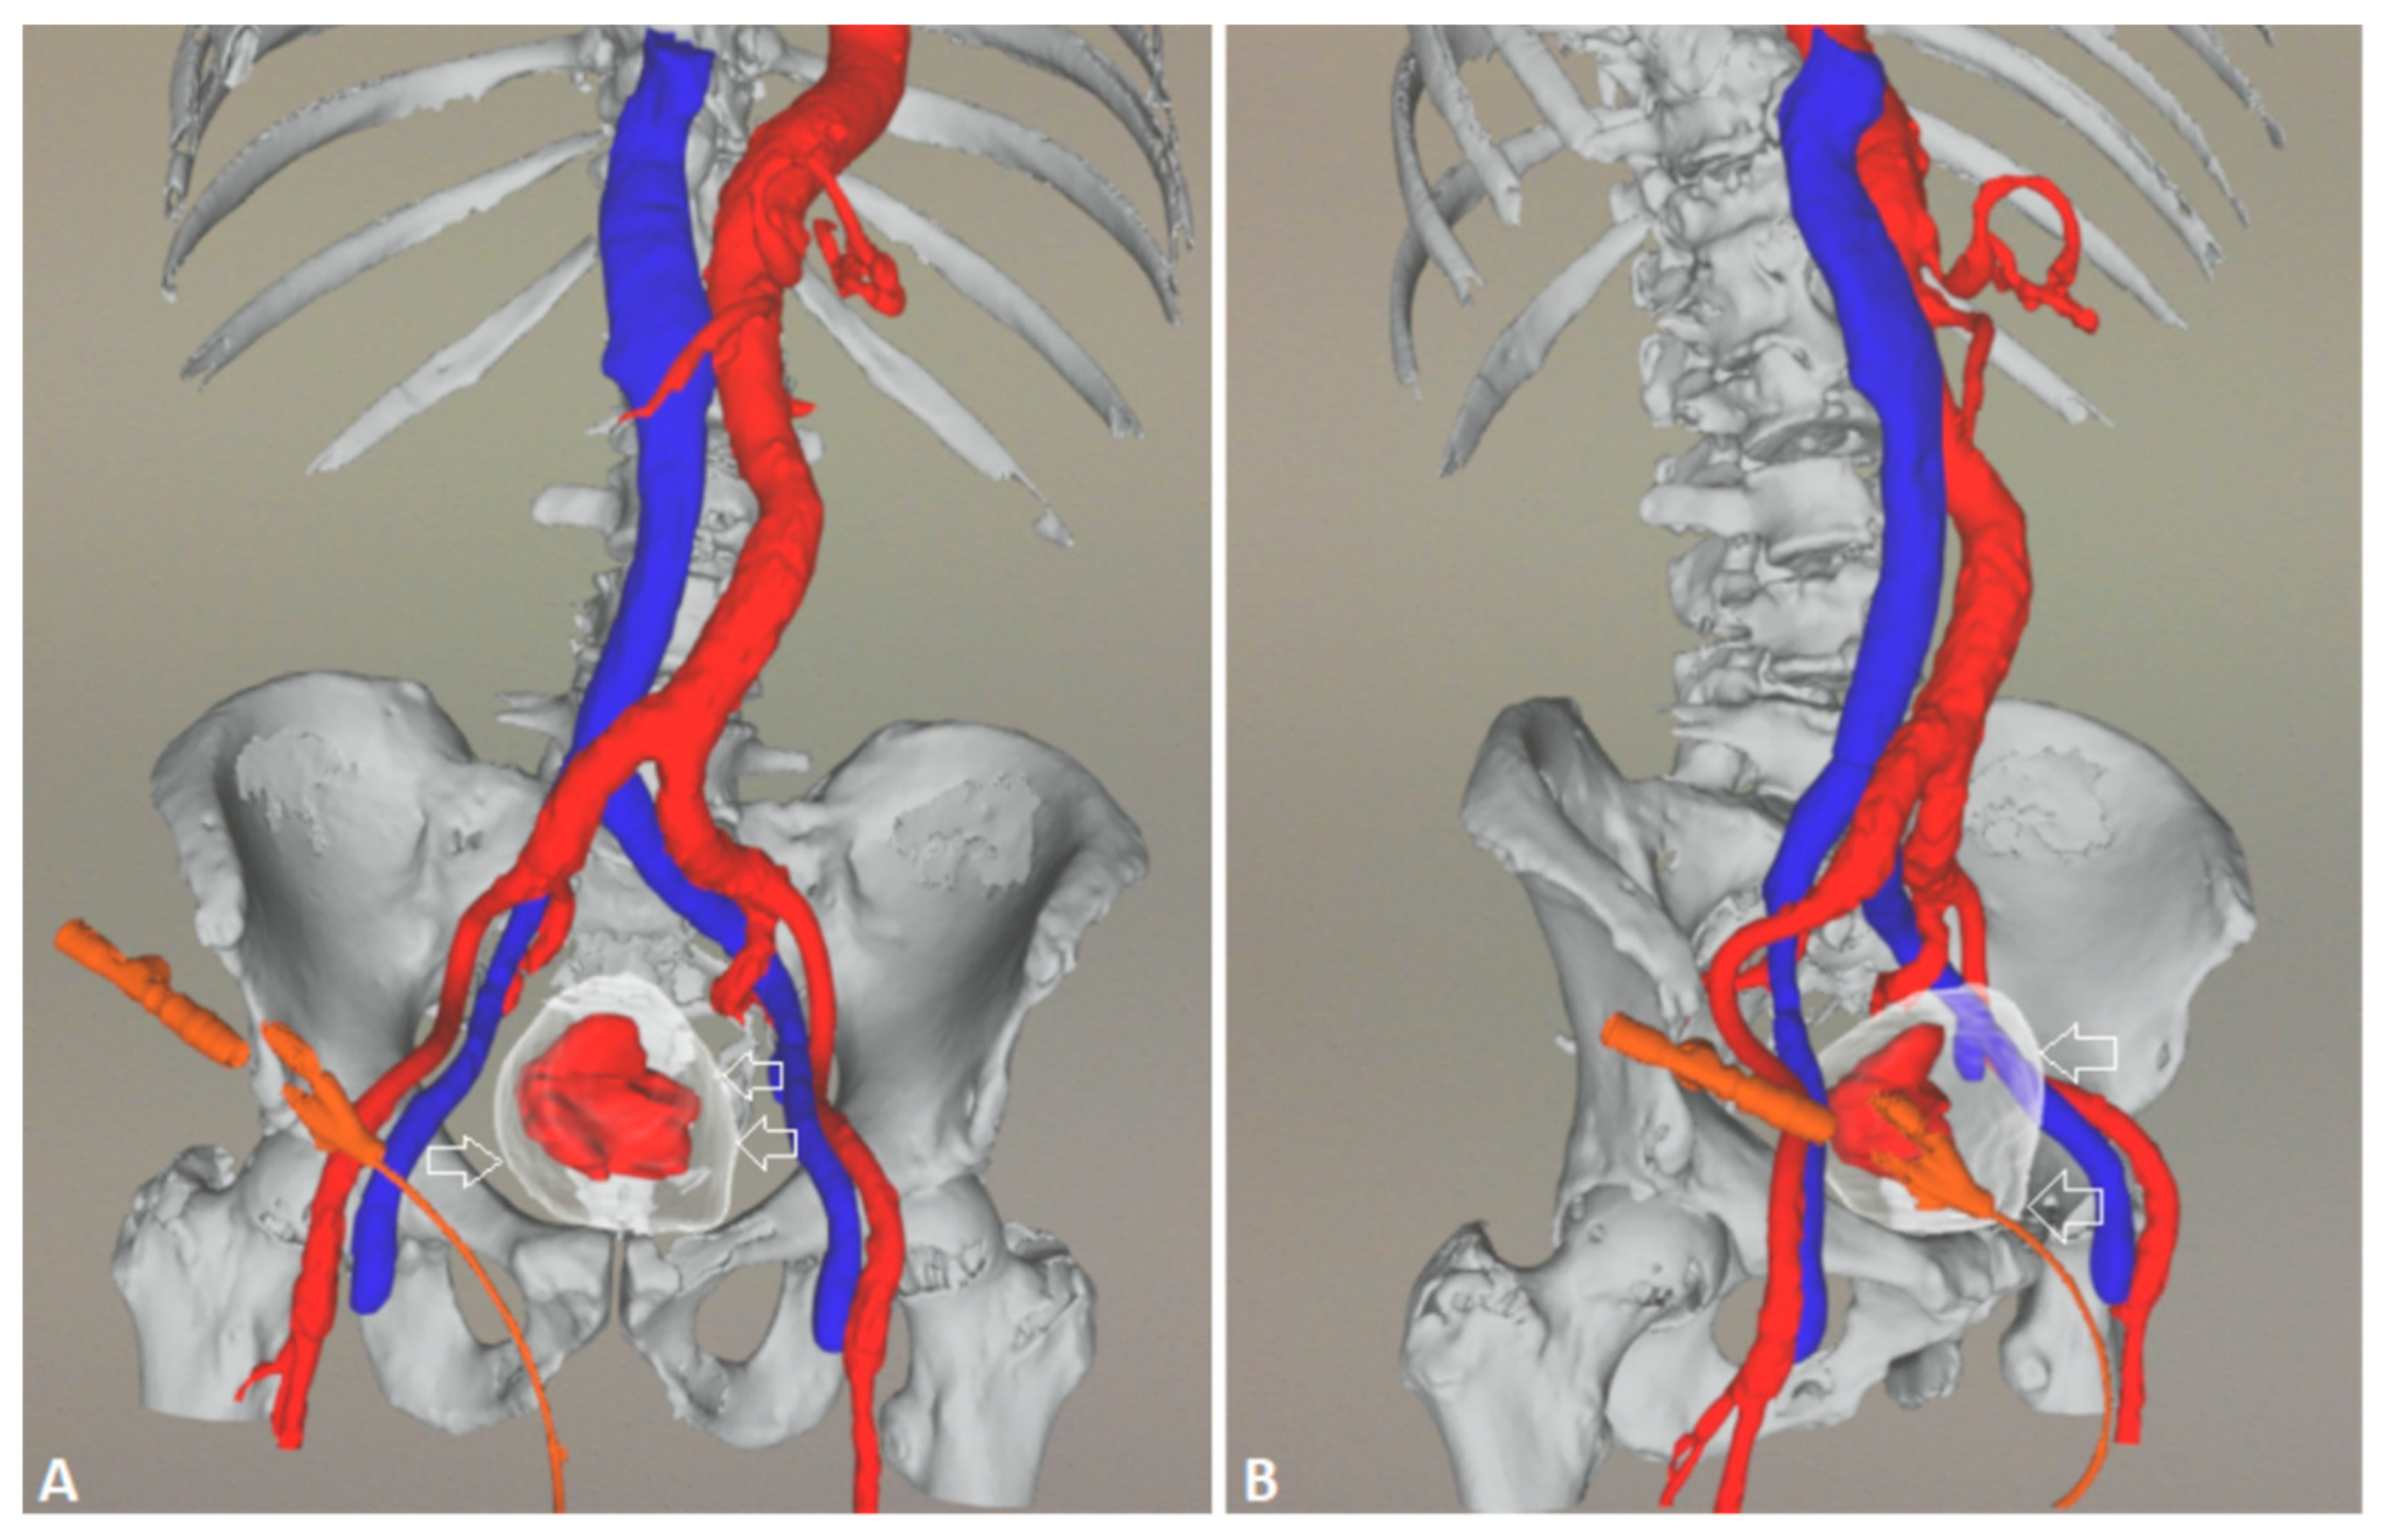

5.1. Technical details of PAE